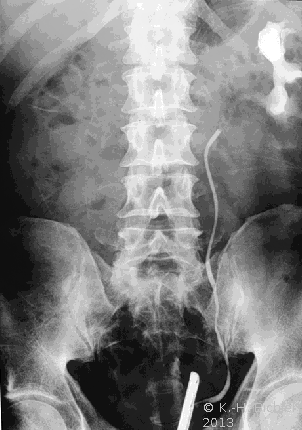

Ein i.v.-Pyelogramm kann im Rahmen der differentialdiagnostischen Abklärung des Flankenschmerzes indiziert sein (Abbildung). Sofern schon eine ausgeprägte Niereninsuffizienz vorliegt, sollte die Abklärung mit einem retrograden Pyelogramm erfolgen (Abbildung 5).